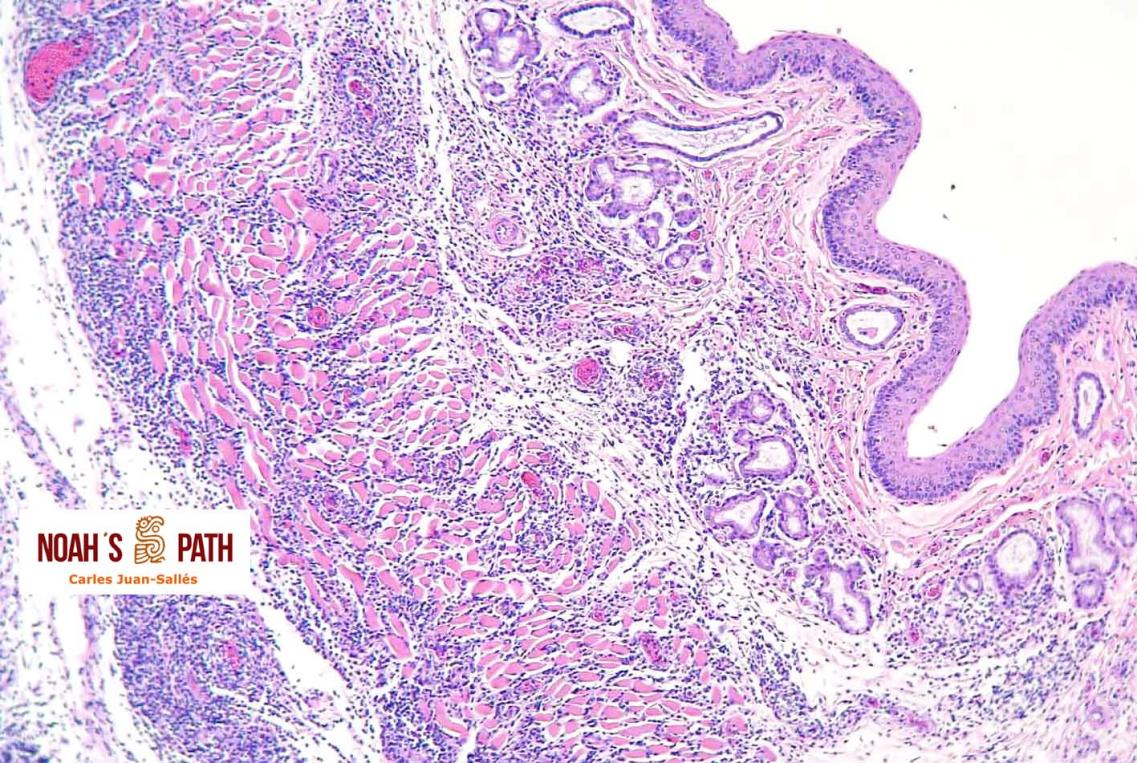

Nocardiosis en hurones, estudio recién publicado (J Comp Pathology): una de las infecciones más frecuentes en hurones en España

La histopatología, herramienta básica en diagnóstico: tromboembolismo portal por nematodos en el hígado de un armadillo